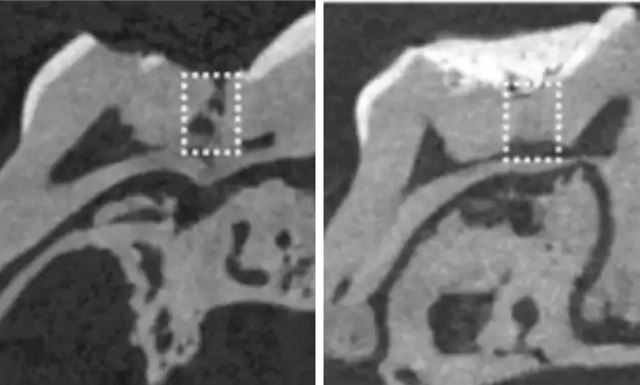

但是Tideglusib這種藥物,卻有促進象牙質自我再生的速度,研究人員將膠原蛋白海綿體浸泡在這種藥物中,然後塞進白老鼠的蛀牙中,奇妙的事情發生了,白老鼠的蛀牙就不藥而癒了!

它的原理其實非常簡單,就是結合Tideglusib會活化象牙質再生的特性,加上可以自我分解的海綿膠體。只要將這個浸過Tideglusib的海綿放到蛀牙處,就可以讓牙齒自我再生!可以完全取代現在補牙的方式!我們再也不用挨著補牙時的不舒適感與異物感,只要塞個海綿就萬事OK!!